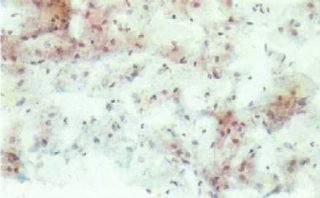

Esfregaço vaginal de menina antes da puberdade

[singlepic id=505 w=320 h=240 float=center]

Esfregaço vaginal de menina durante a puberdade